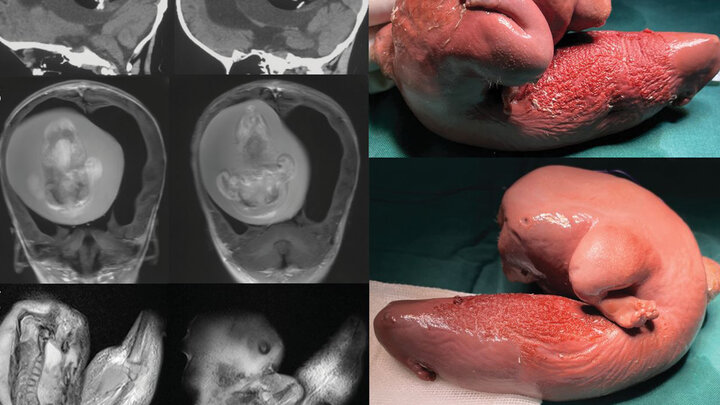

به گزارش شهرآرانیوز - پزشکان دانشگاه فودان در شانگهای متوجه چند مشکل در یک دختربچه یک ساله مانند سر بیش از حد بزرگ و اختلال در مهارت های موتور حرکتی شدند. به نوشته نشریه IFLScience سی تی اسکن های سر این دختر بچه نشان داد مغز او تحت فشار است. علاوه بر آن تجمع مایعات سبب رشد بیش از اندازه در بطن های مغز شده بود.

محققان طی فرایند جراحی متوجه شدند رشد بطنی در حقیقت قل متولد نشده این کودک بوده است. هرچند بخش اعظم جنین تکامل نیافته بود اما به نظر می رسید اعضای بخش بالایی بدن و اندام های فرعی مانند انگشتان شکل گرفته اند.

چنین مواردی در متون پزشکی بسیار نادر هستند. موارد جنین داخل جنین در مراحل اولیه بارداری دوقلوها و زمانی اتفاق می افتد که بلاستوسیست (خوشه ای از سلول های در حال جدا شدن به وسیله تخمک بارور) به درستی انجام نمی شود.

در نتیجه این امر یکی از جنین ها دیگری را دربر می گیرد. هرچند باید اشاره کرد جنین دربرگرفته شده نمی میرد بلکه به دلیل خون رسانی منظم از قل دیگر، زنده می ماند اما رشد نمی کند.

در این نمونه تحقیقی فقط اشاره شده کودک یک ساله بهبود یافته است. هرچند این عمل جراحی بسیار سخت است، اما ندر مونه های پیشین بهبود کامل حاصل شده بود.